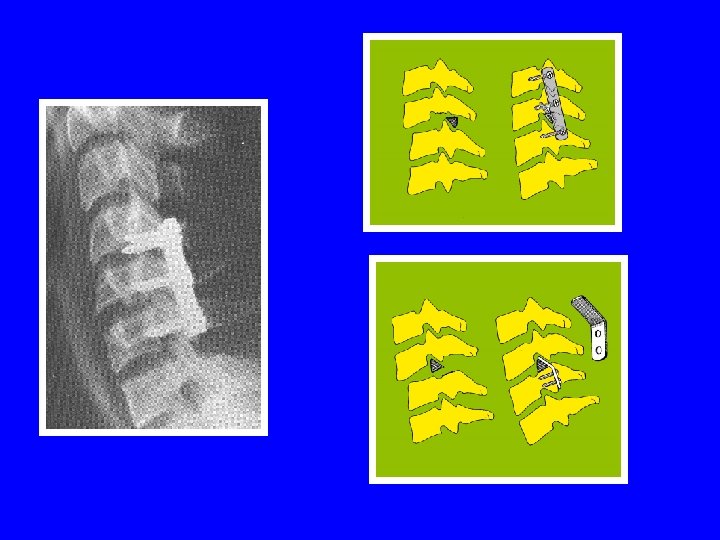

STABILISATION DU RACHIS VOIE ANTERO-LATERALE (Smith et Robinson) stabilisation par greffe autologue + ostéosynthèse par plaque vissée dans les corps VOIE POSTERIEURE (Roy-Camille) stabilisation par plaques vissées dans les massifs articulaires stabilisation par crochets lamaires stabilisation par laçage interlamaire

LE CHOIX DE LA VOIE D ’ABORD C ’est le plus souvent la voie antéro-latérale qui est utilisée. - c ’est la plus simple - elle respecte la musculature postérieure du cou - elle assure une stabilisation de qualité sur le segment vertébral le plus solide - elle permet, associée aux manœuvres de réduction, de résoudre la quasi totalité des situations rencontrées

LE CHOIX DE LA VOIE D ’ABORD La voie postérieure est réservée: - aux compressions postérieures non réductibles - aux luxations anciennes irréductibles par les manœuvres - aux fractures articulaires empéchant la réduction d ’une luxation